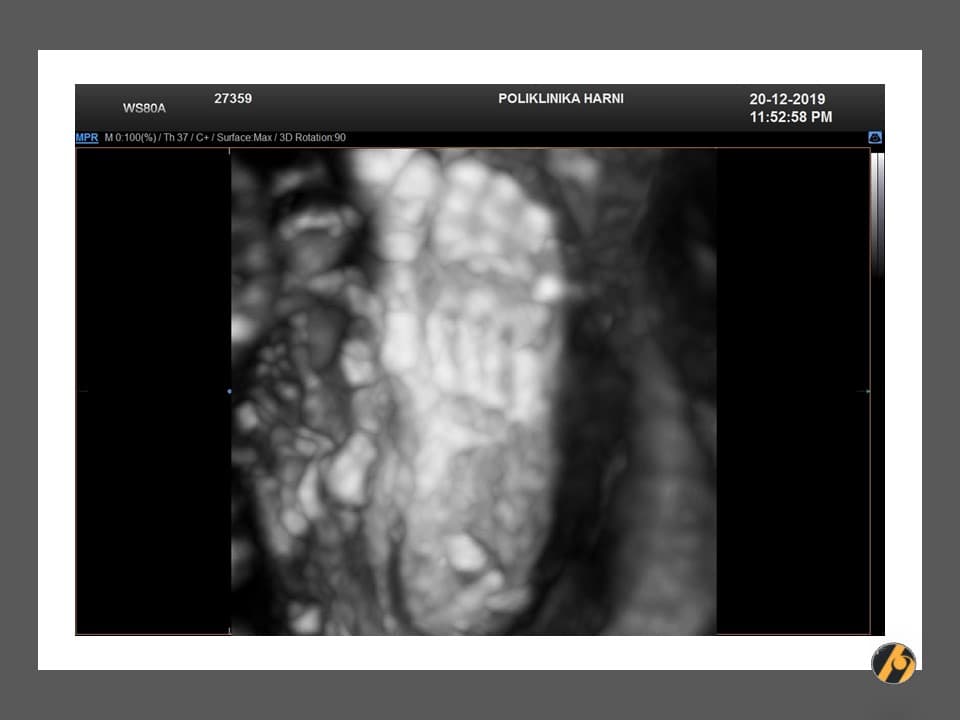

Najkasnije u 32. tjednu uredne trudnoće, planira se napraviti treći obavezni ultrazvučni pregled. Na ovom pregledu promatraju se položaj djeteta, položaj i izgled posteljice, te količina plodne vode. Ukoliko postoje nepravilnosti, ultrazvučni pregled će se ponoviti u kraćem vremenskom periodu. Osim položaja bebe i posteljice, uobičajeno vrše se standardna mjerenja i procjena rasta djeteta.